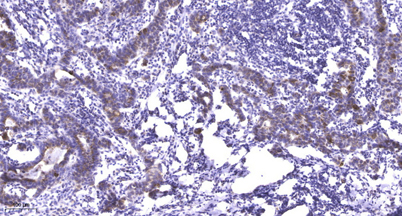

Product name: Plakophilin 2 rabbit pAb

Dilutions: WB 1:500-2000;IHC-p 1:50-300; ELISA 2000-20000

Immunogen: The antiserum was produced against synthesized peptide derived from human PKP2. AA range:632-681